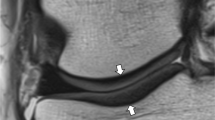

If successfully implemented into clinical routine, cartilage mapping has many potential uses. Clinically meaningful colour scales could be applied to cartilage mapping overlays for qualitative assessment (shown in Fig. 1), and quantitative data could be analysed to help in clinical decision making and outcome tracking. Quantitative mapping could be utilized in treatment planning and tracking a patient’s progress over time. The current biochemical state of the cartilage may also be related to clinical outcome; however, this has yet to be determined and few studies with histological correlation have been performed in vivo in the human. In addition, the health of the cartilage may help determine whether a conservative approach such as physical therapy can be attempted or if surgical intervention is needed. It may be theorized, however, as we currently do not fully understand the cartilage biochemical alterations that occur in each of these scenarios (i.e. osteoarthritic cartilage, early OA, damaged cartilage, post-operative, non-operative intervention, and pharmaceutical and therapeutic intervention), that each may have a different effect on the T2 value and that the research community should strive for understanding of this. It may also be reasonable, taking into account the parameters that may introduce variability and affect reproducibility, that a specific method of analysis (i.e. determination of internal healthy control cartilage; subregion/ROI analysis) may be appropriate for different situations (e.g. follow-up evaluation after cartilage repair surgery, monitoring cartilage following an injury for development of OA etc.) as determined by a surgeon or researcher. This notion may facilitate understanding of individual circumstances and reasons to optimize reproducibility.